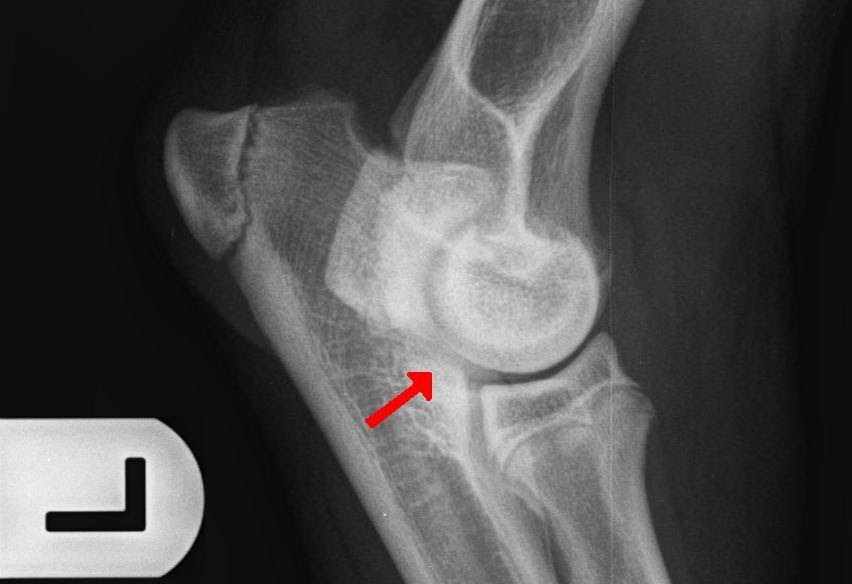

Для диагностики дисплазии локтевого сустава у неаполитанских мастифов обычно используют рентгенографию, которая позволяет оценить состояние сустава и определить наличие патологических изменений. Лечение может включать консервативные методы, такие как физиотерапия и применение препаратов для облегчения боли. В более серьезных случаях может потребоваться хирургическое вмешательство.